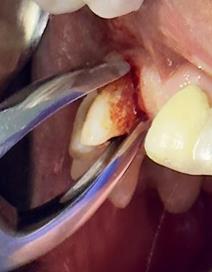

Sindesmotomía con un periostótomo de molt # 9, posteriormente se realizó la luxación con un elevador recto, buscando el punto de apoyo, seguido se efectuó la prensión con el fórceps 150 en el diente con sumo cuidado de no tocar la encía colocándolo hasta el cuello dental, haciendo movimientos de lateralidad y rotación hasta lograr la dilatación del alveolo, y finalmente la tracción del órgano dentario, observando que la raíz este integra, y que estructuras alrededor estén conservadas, de la misma forma se revisó el alveolo en busca de la presencia de granulomas o espículas óseas, una vez ya revisado se procedió al curetaje, con una cucharilla de lucas, se introdujo y se dio paso al retiro del exudado purulento, se realizó irrigación del alveolo con solución fisiológica, una vez limpio se realizó una sutura simple con sutura nylon, seda # 3/0 en el medio del alveolo con la finalidad de aproximar rebordes, evitar su contaminación por el ingreso de comida, además generar una mejor cicatrización en una zona estética , finalmente se aplicó presión por medio de una gasa que mordió el paciente por un lapso de 30 minutos, para contribuir con una hemostasia adecuada.

Figura 6. Sindesmotomía, luxación y prensión del incisivo lateral superior derecho pieza N.º 1.2

Elaboración: Los autores.